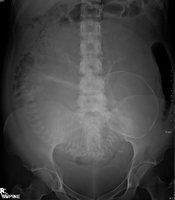

A radiograph is an X-ray image obtained by placing a part of the patient in front of an X-ray detector and then illuminating it with a short X-ray pulse. Bones contain much calcium, which due to its relatively high atomic number absorbs x-rays efficiently. This reduces the amount of X-rays reaching the detector in the shadow of the bones, making them clearly visible on the radiograph. The lungs and trapped gas also show up clearly because of lower absorption compared to tissue, while differences between tissue types are harder to see.

Radiographs are useful in the detection of pathology of the skeletal system as well as for detecting some disease processes in soft tissue. Some notable examples are the very common chest X-ray, which can be used to identify lung diseases such as pneumonia, lung cancer, or pulmonary edema, and the abdominal x-ray, which can detect bowel (or intestinal) obstruction, free air (from visceral perforations) and free fluid (in ascites). X-rays may also be used to detect pathology such as gallstones (which are rarely radiopaque) or kidney stones which are often (but not always) visible. Traditional plain X-rays are less useful in the imaging of soft tissues such as the brain or muscle.